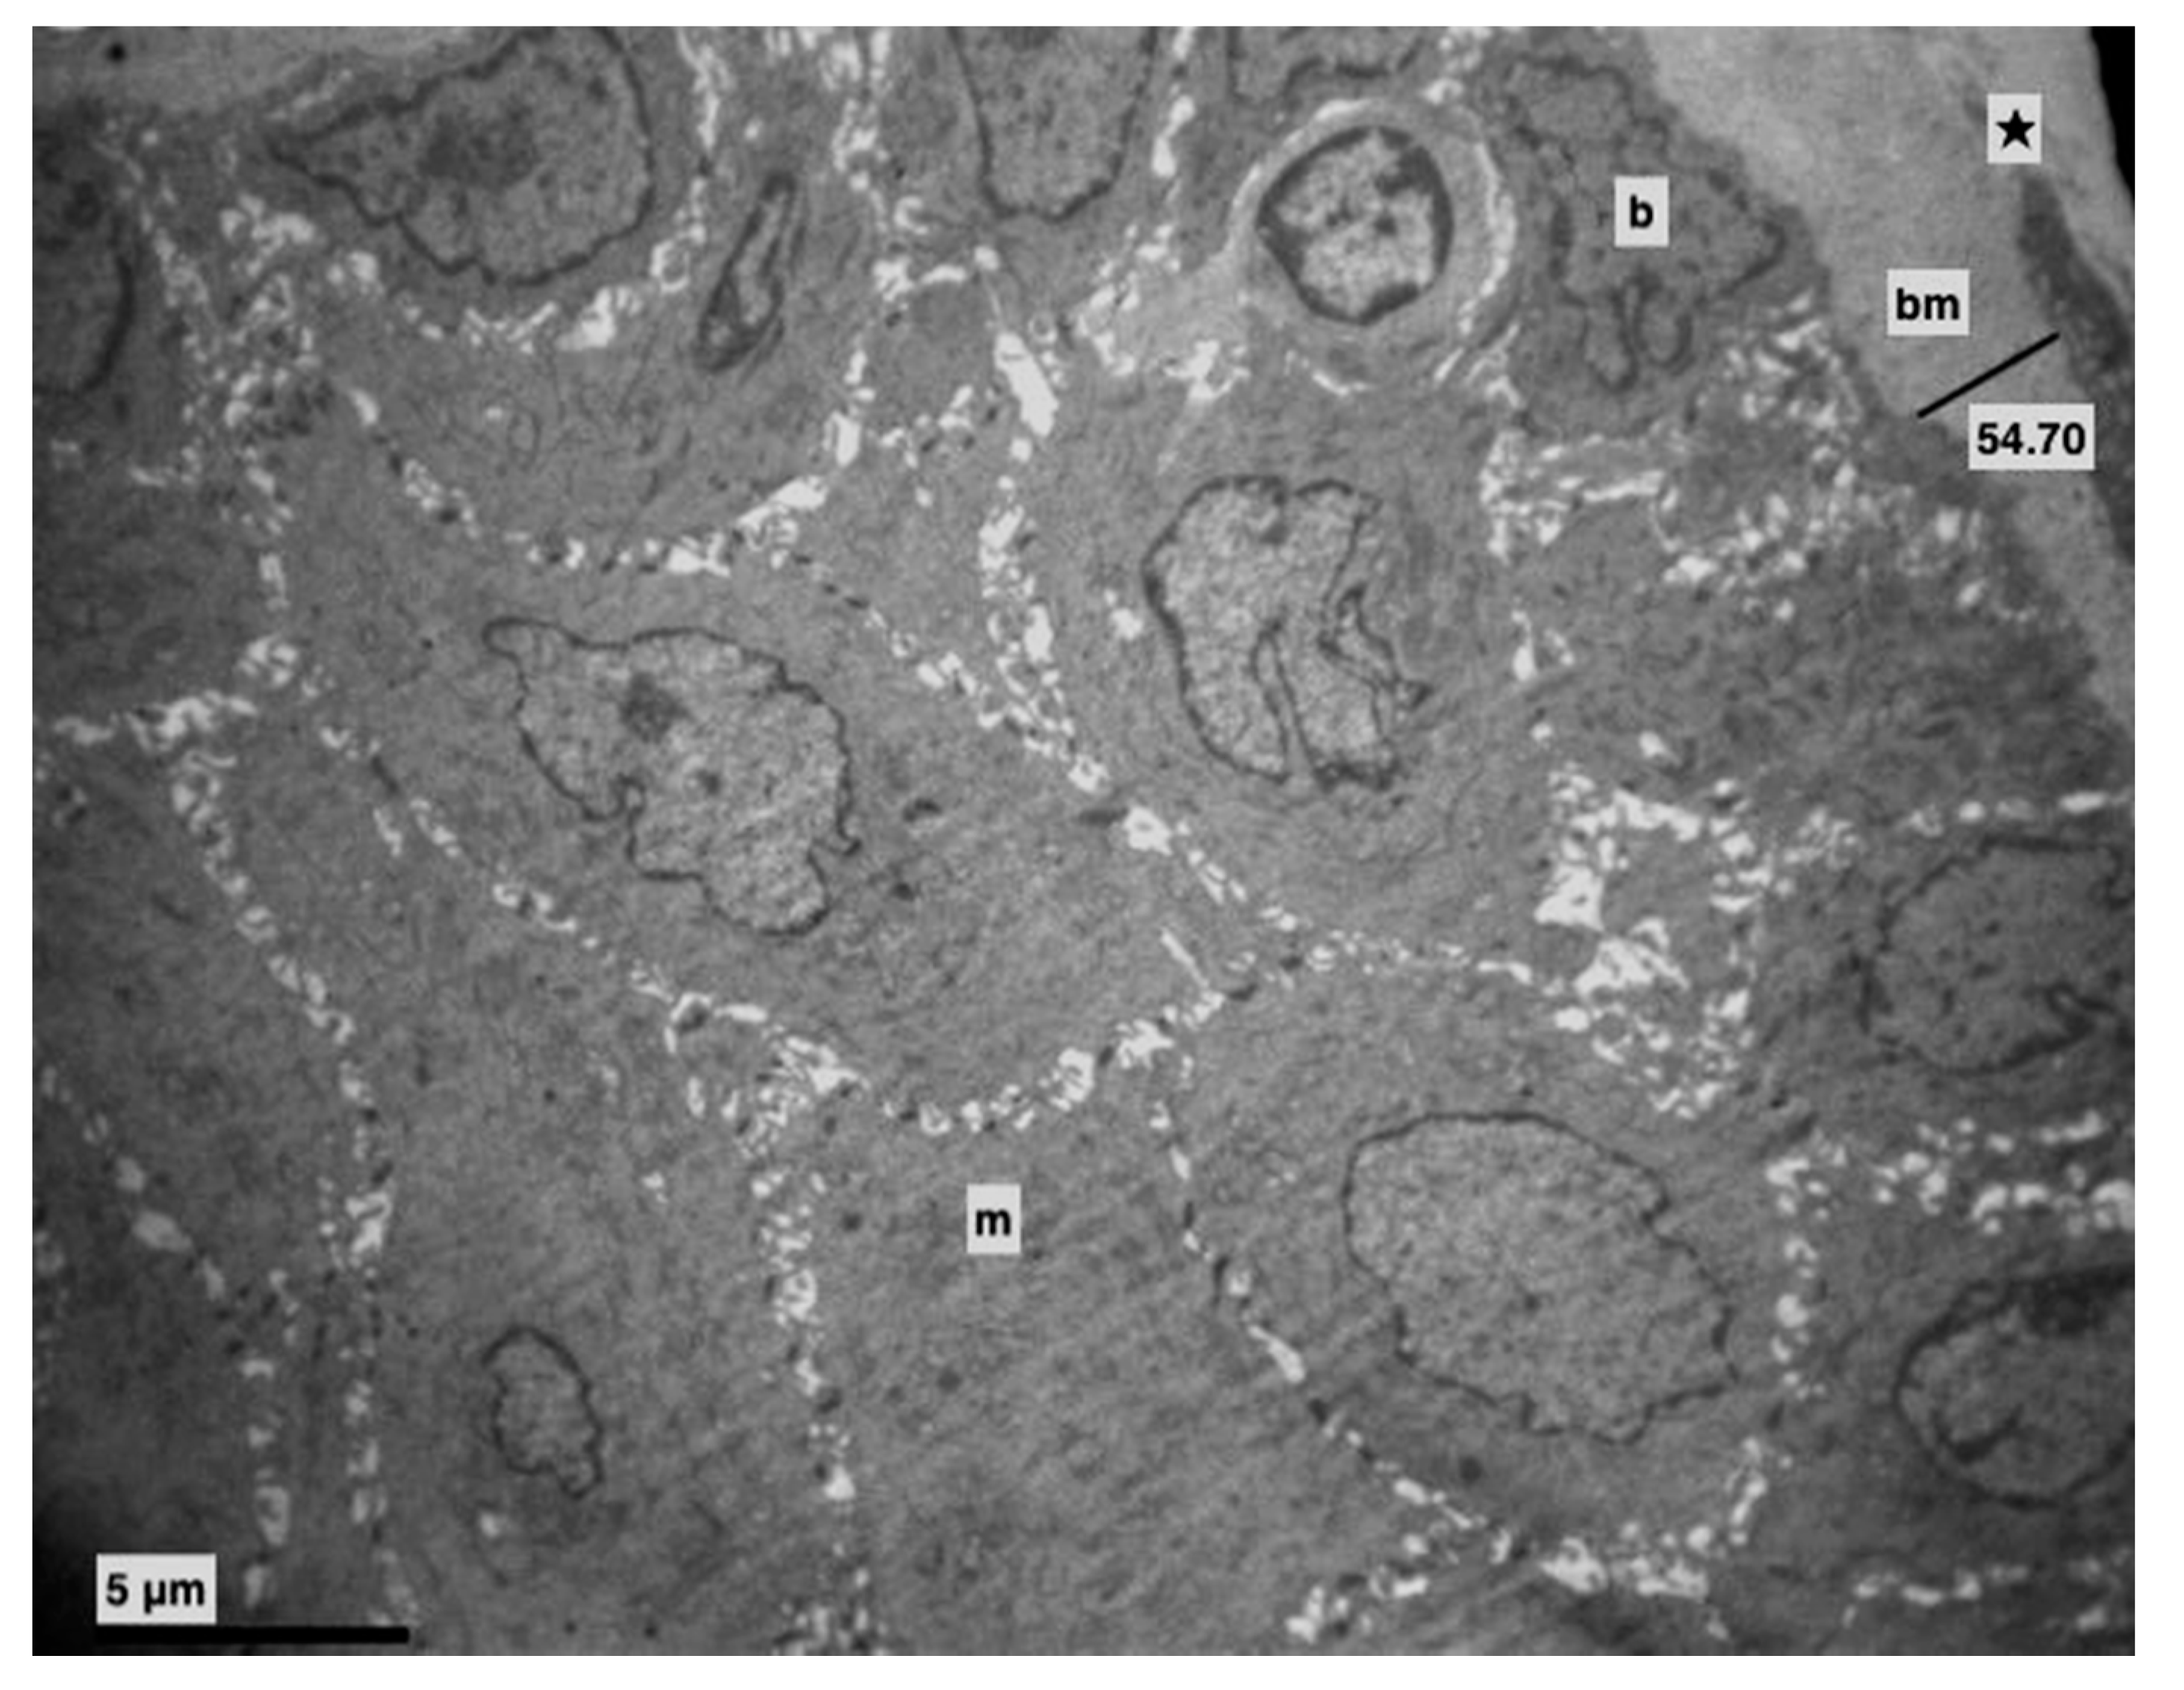

3. Results